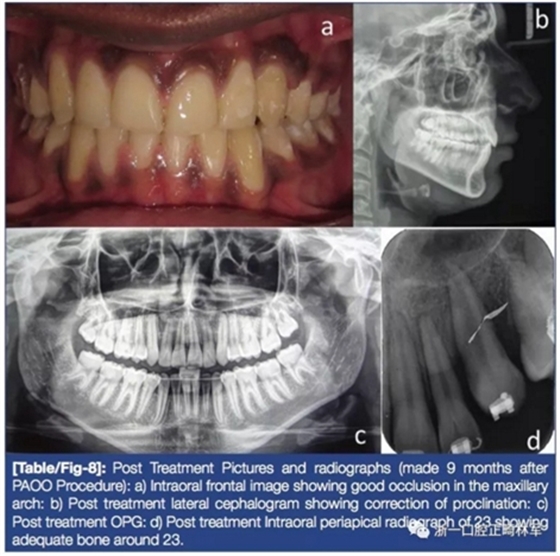

術(shù)后,糾正23旋轉(zhuǎn)(圖6)。有較大旋轉(zhuǎn)量后換用0.017×0.025-in銅鎳鈦絲將23排入牙弓,45天后完成(圖7)。最后階段關(guān)閉間隙,治療結(jié)束(圖8)。保持階段上頜使用Begg環(huán)繞式保持器,下頜使用固定保持器。

5年后隨訪結(jié)果:除了23有輕微的近中腭向旋轉(zhuǎn)外,余均保持穩(wěn)定(圖9)。